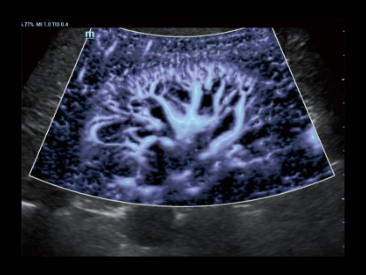

Zupe?nie nowy spos├│b na prezentacji przep?ywu krwi

z wykorzystaniem techniki Color/Power Doppler 2D w wizualizacji 3D

Przypadek kliniczny z wykorzystaniem technologii Glazing Flow (tryb power):

Unaczynienie nerki

Technologia Glazing Flow zapewnia wyra?n? wizualizacj? struktury t?tnicy ?ukowatej i t?tnicy mi?dzyp?atowej mniejszej z widokiem 3D.